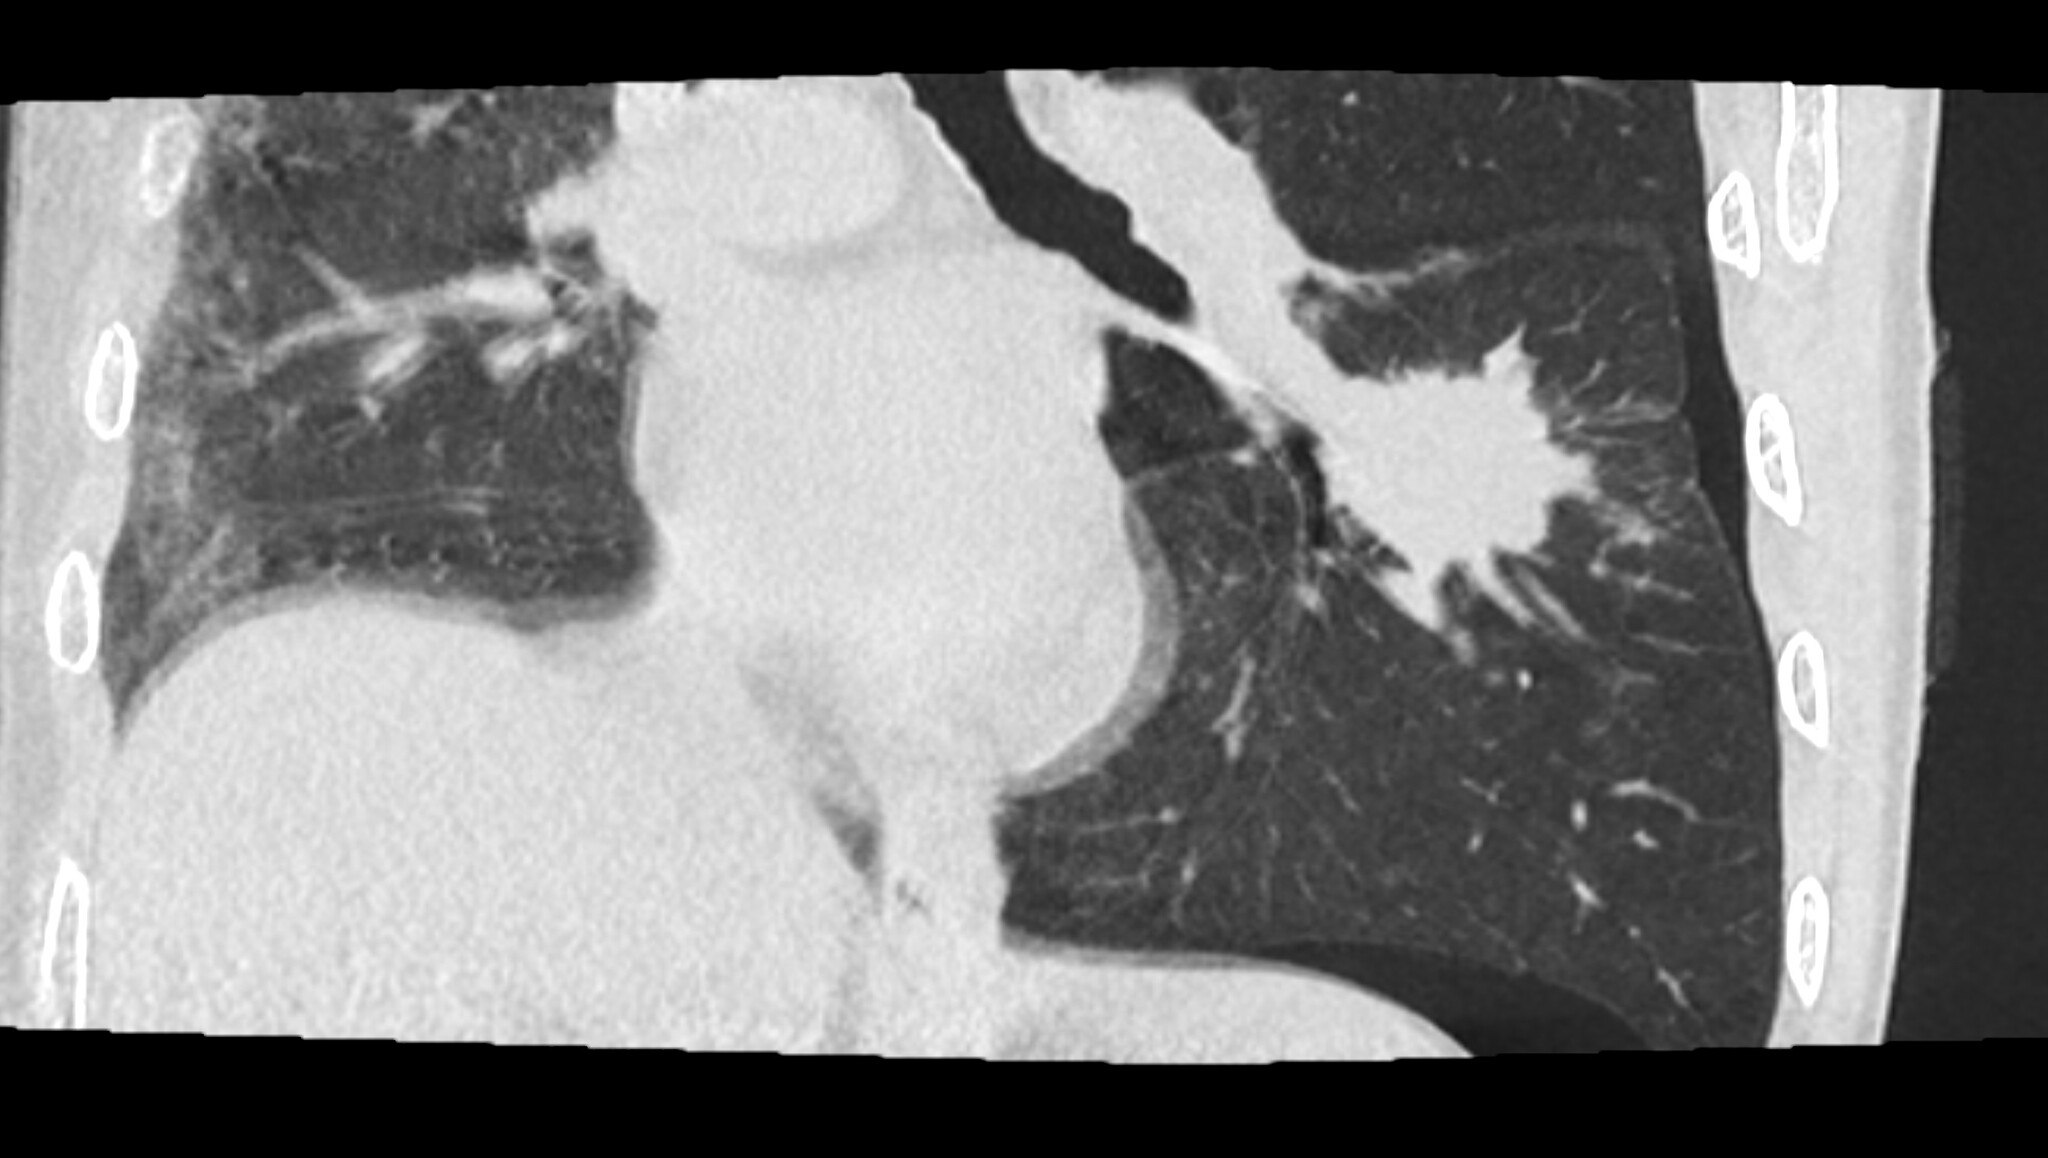

Сегодня мне посчастливилось сделать биопсию лёгкого у мужчины, 68 лет, с подозрением на рак в апикальном сегменте левой нижней доли (на картинках ниже смотрим на правую часть, белое пятно и есть возможное зло). Вроде и образование не шибко маленькое и пункция особых проблем не обещала, но настораживала близость очага к междолевой борозде, которую имелись все шансы повредить, что, статистически, является предпосылкой к пневмотораксу (воздух в плевральной полости):